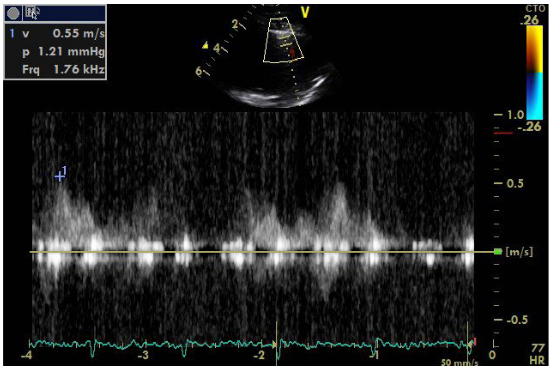

An additional element is the localization of the stenosis in the initial part of renal vessel, as opposed to FMD that commonly affects the middle and peripheral portions. The sudden deterioration of renal function within a short period of time also advocates for atherosclerosis as the FMD has a slower course. It is noted that atherosclerosis may lead to complete abstraction/thrombosis over time, rarely occurring FMD. Finally, the immunological test performed to rule out vasculitis was negative. Renal arteriography indicated a 99% stenosis to the left and the patient underwent a successful stent implantation. After angioplasty, blood pressure returned to normal and the patient did not receive any medication. It is worth noting that despite the presence of stage III hypertension and the underlying disease, the patient did not show signs of diastolic dysfunction in the Doppler (Figures 8–10), nor any signs of hypertrophic left ventricle in ECG.  Not a patient with long-standing uncontrolled hypertension. Moreover, to stress echocardiography with doboutamine there were no wall motion abnormalities, while coronary flow reserve was normal (CFR LAD=2.2) (Figure 11A & 11B).

Figure  7 Doppler of mitral valve inflow.